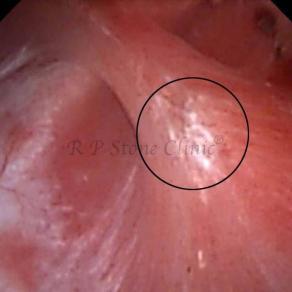

These images are taken as snap shots from the video recording of RIRS Surgery done at our hospital. These are Randall’s Plaques seen with Digital FLEX XC & Digital FLEX XC S. The cream or whitish patches are seen on the tips of RENAL PAPILLAE as seen in images below.

The Below Images Show Small Stones attached to the Renal Papillae.